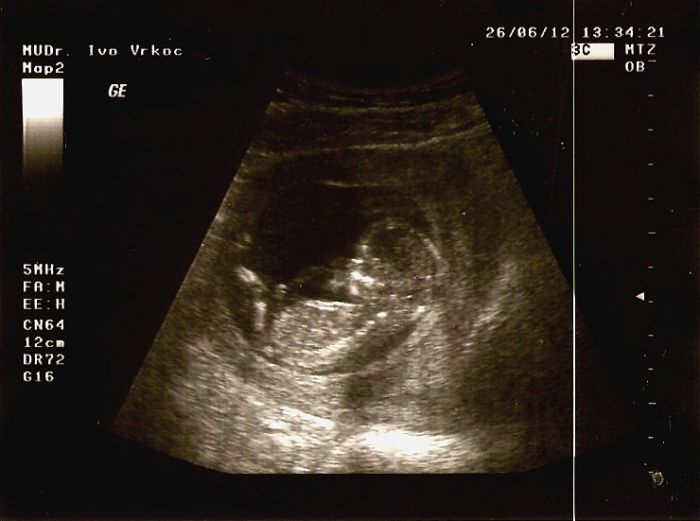

Hematom na placentě ve 12. týdnu těhotenství

Dobrý den.Máte nějakou zkušenost se sraženinou na placentě,která se pak z placenty a z těla odloučila? Tenhle pátek mě postihli strašně bolestivé křeče v podbřišku,kdy jsem se se slzami svíjela na posteli a celou noc bolesti pokračovali + je doprovázelo špinění a hnědé sraženiny.Druhý den jsem ráno zavítala na gyn.pohotovost a lékař mi řekl že to není tak neobvyklé a do zprávy napsal:Vitální gravidita odpovídající 11-12 týdnum těhotenství.Placenta na zadní stěně v oblasti vnitřní branky-hematom asi s 1 cm hranou.Doporuč.klid a magnesium.Dnes už nešpinim,ale pořád mě v podbřišku občas píchne a mám pochopitelně strach že se křeče opět dostaví.Srdeční činnost malého byla dobrá tak doufám že vše dobře dopadne.Za dva dny mám kontrolu v těhu.poradně.Děkuji za radu :(

Tak po včerejším krvácení kdy jsem dostala injekci na zástavu jsem se dozvěděla že mám další hematom který má 2x1 cm.Mám brát magne B6 3x denně a jen ležet a nikam nechodit.Za dva týdny mám kontrolu.Lékař říkal že když budu odpočívat že by se měl hematom vstřebat,ale že když to zanedbám mohou se odloučit plodové obaly a můžu potratit :( Tak doufám že vše dobře dopadne,protože se na mrňouse moc těším,ale zároveň mám hrozný strach.Teď už jen lehce hnědě špinim včerejší zbytky té krve.